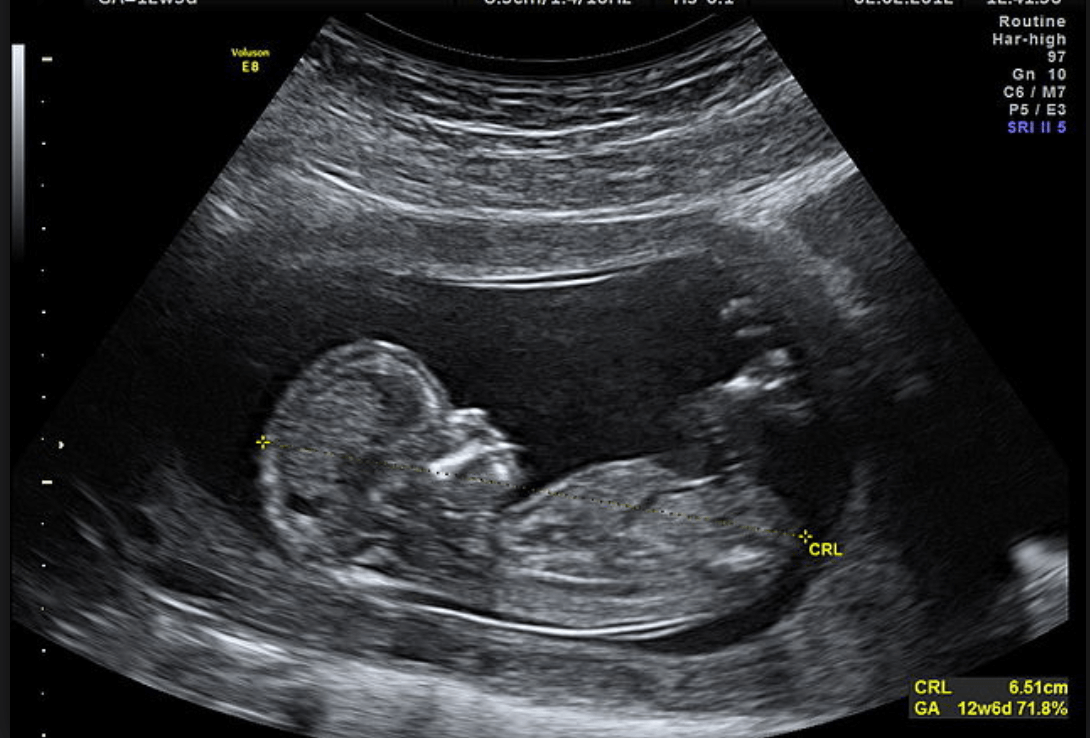

Échosonogramme du premier trimestre

Cette échographie est réalisée afin de voir si la grossesse est viable. On observe s’il y a un embryon vivant, s’il a un sac amniotique et le nombre d’embryons présents. De même, on mesure la taille du fœtus, du crâne au coccyx pour déterminer le moment de la gestation.